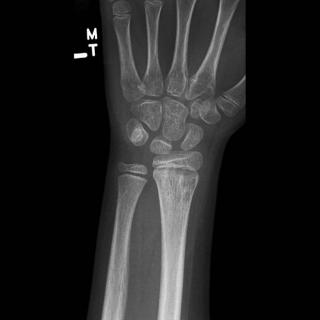

Инструментальная визуализация начинается с рентгенографии, которая проводится с использованием обзорных снимков в двух проекциях — прямой и боковой, а при подозрении на хроническое течение дополняется прицельной рентгеноскопией с контрастным исследованием свищевых каналов. Обзорный режим позволяет определить деструкцию костной ткани, периостальные реакции и наличие секвестров. Контрастное исследование уточняет характер и распространённость воспалительного очага, особенно при наличии осложнений.

Рентгенограмма выявляет следующие анатомические признаки:

- Очаговый остеопороз в диафизарной и метафизарной зоне плечевой кости, проявляющийся как снижение плотности трабекулярного рисунка, часто служит первым признаком воспаления.

- Остеолитические зоны с нечёткими границами, визуализирующиеся как просветления неправильной формы, указывают на прогрессирующее разрушение костной структуры.

- Слоистые периостальные наслоения по типу «луковичной оболочки», определяемые при хроническом процессе, свидетельствуют о многократной стимуляции надкостницы.

- Формирование секвестров, отделённых от окружающей кости, проявляется в виде плотных участков с чёткими границами на фоне остеопороза.

- При контрастной рентгеноскопии возможна визуализация симптома «контрастного хода» — заполнение свищевого канала контрастом, что подтверждает наличие хронической формы остеомиелита.

Рентгенологическое исследование позволяет детально визуализировать следующие диагностические параметры остеомиелита плеча:

- Точные очаги остеолиза, их локализация и распространённость определяются на обзорных снимках, что критически важно для верификации диагноза и планирования лечения.

- Периостальные реакции, фиксируемые при воспалительном процессе, дают представление о его продолжительности и стадии, а также позволяют отличить острые изменения от хронических.

- Формирование секвестров как специфических признаков затяжного течения доступно для надёжной оценки, особенно в сравнении с динамическими снимками.

- Контрастное исследование при наличии свищей визуализирует направления воспалительных трактов и их связь с очагом деструкции, дополняя клиническую картину.

Рентгенографическая визуализация имеет ряд ограничений, и с её помощью не всегда удаётся точно визуализировать следующие аспекты остеомиелита плеча:

- Начальные изменения в костном мозге и сосудистые нарушения не отображаются на снимках, что снижает чувствительность диагностики в остром периоде.

- Мягкотканевые осложнения, такие как параоссальные абсцессы и инфильтраты, не определяются при стандартной рентгенографии и требуют дополнительной оценки.

- Функциональные характеристики воспаления, включая гиперемию и выраженность отёка, остаются вне зоны визуализации, особенно в ранние сроки заболевания.

- Лучевая нагрузка при двупроекционной визуализации плеча составляет от 0,1 до 0,2 мЗв в зависимости от толщины мягких тканей и количества выполненных проекций.